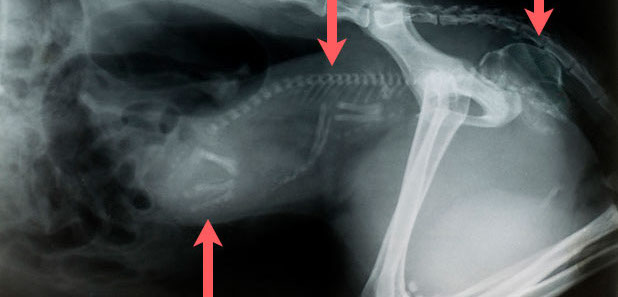

Erstgebärender Hund mit einzelner übergroßer Frucht, Welpe steckt im Geburtskanal